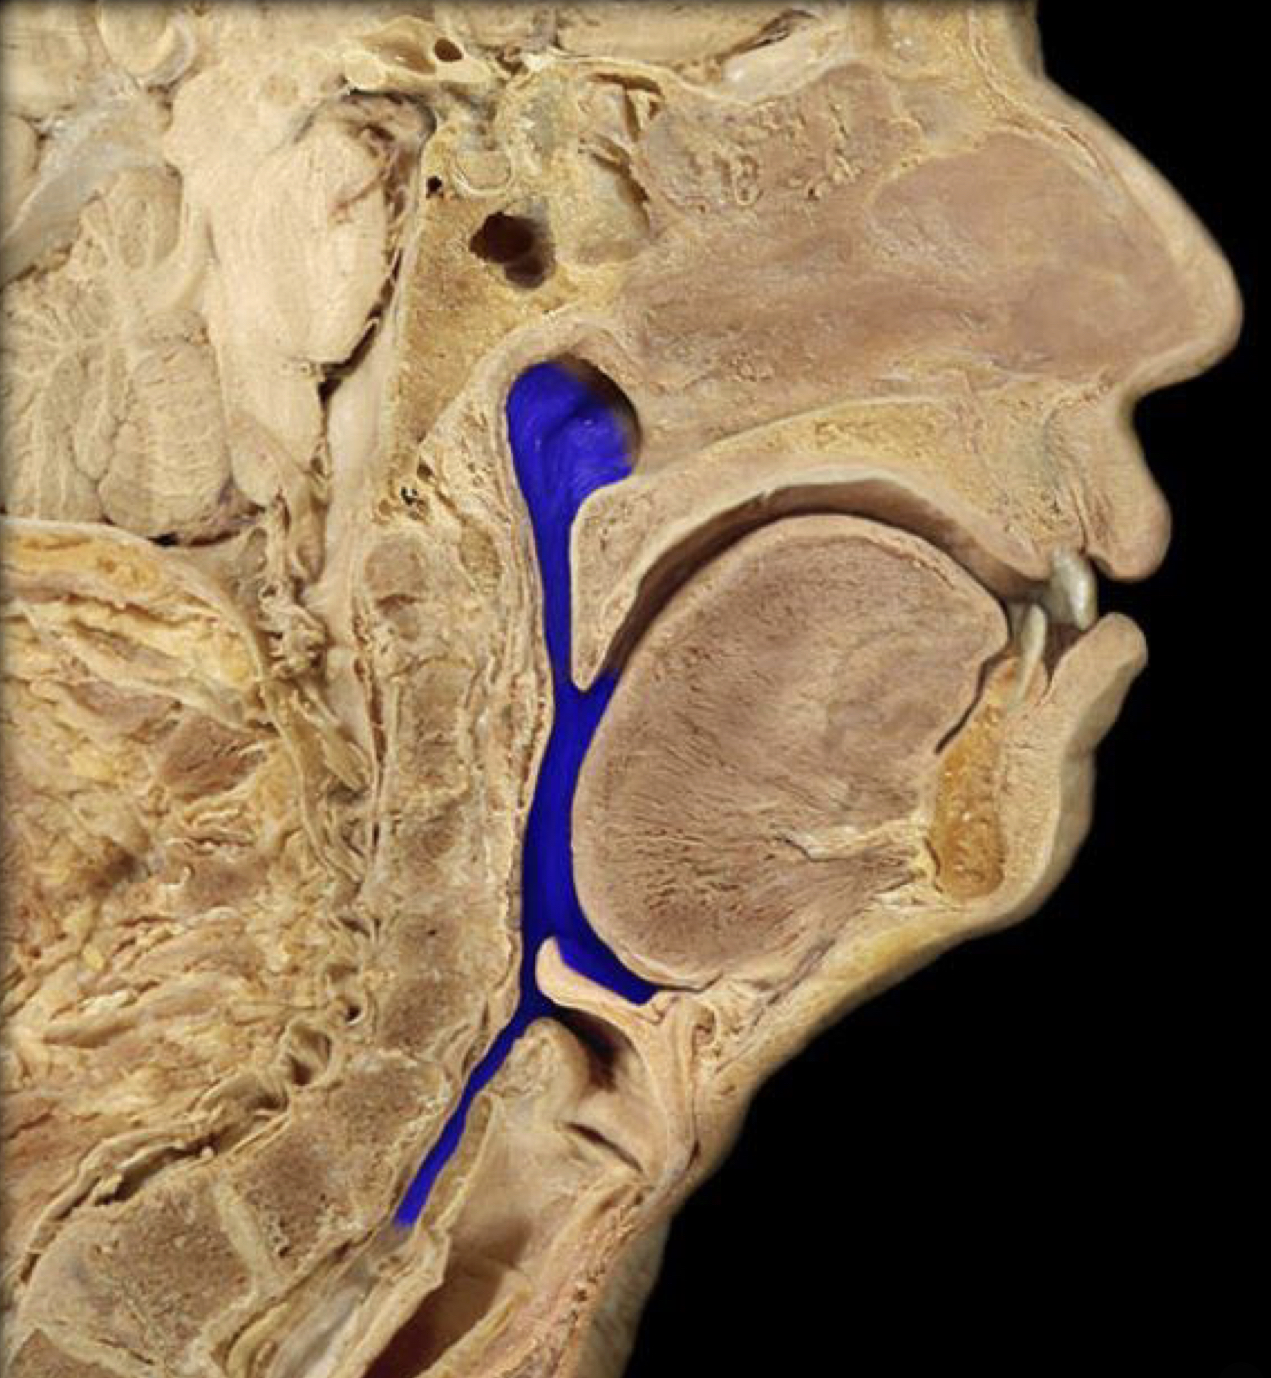

What structure is highlighted in blue?

Pharynx